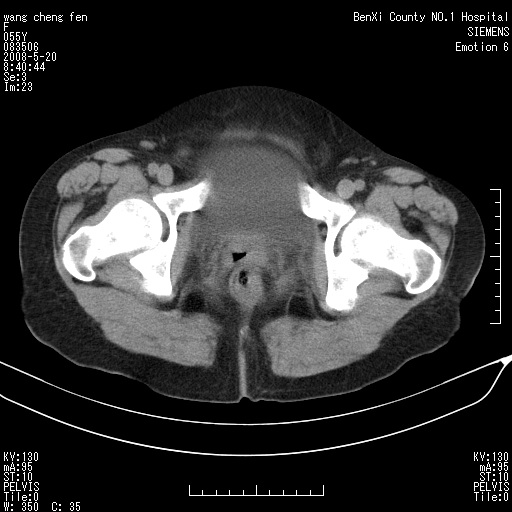

女、绝经后阴道流血3个月

宫颈略萎缩、宫颈前唇及阴道前臂可初级结节。

宫颈好像也有问题吧,大家在仔细看看,另外彩超回报为卵巢占位。建议ct。

支持浆膜下子宫肌瘤.之前由于网络原因未看全图片,现在重看,宫颈见一类圆形低密度影,增强轻度强化,低于肌层强化,宫腔扩大,考虑宫颈癌伴宫腔积液可能性大.

1,宫颈部占位,宫颈癌?2,左侧附件区囊实性占位,界较清,实质部分强化明显。考虑浆膜下或阔韧带肌瘤囊变可能大。囊腺类肿瘤不除外。